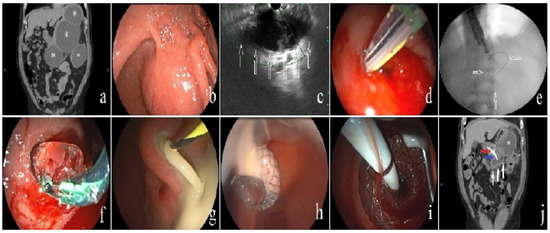

2. Materials and Methods

3.2. Initial Outcomes of Endoscopic Intervention

3.3. The Addition of Percutaneous Intervention as a Step-Up Approach

3.4. Outcomes of Complications, Recurrence, and Follow-Up